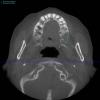

SergeyAL Опубликовано 28 мая, 2013 Поделиться Опубликовано 28 мая, 2013 на кт представлена ситуация до пластики в области 26, 27 зубов по косой линии проведен забор костного блока, блок разделен на пластины, с пластин получена костная стружка проведен вертикальный разрез с преддверия с переходом на окклюзионную поверхность гребня и на 0,5 см на небную поверхность проведена ШИРОКАЯ ОТСЛОЙКА: вестибулярно до бугра, окклюзионно до бугра, небно почти до небного шва и до бугра, слизистая должна сниматься с гребна как чулок (на отек не влияет, т.к. нет послабляющих разрезов надкостницы) из пластин сформирован каркас, внесена костная стружка, через этот же доступ проведен открытый синуслифт, введен синтетическим остеозамещающий материал рана ушита простыми узловыми швами за счет перемещения тканей в небную сторону со сторны преддверия через 4 месяца кт для сравнения, и имплантация через 4 месяца протезирование сначала временное, затем постоянное 17 Ссылка на комментарий